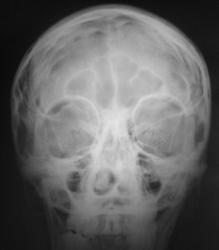

Пациент в ургентном порядке, после ДТП был доставлен в ЦРБ в ночное время. Был вызван "ургентный лаборант" для рентгенографии черепа. Пациент без сознания. С учетом состояния пациента рентгенография произведена в нестандартных проекциях - "задняя прямая".

А что скажите по поводу пирамидки и орбиты справа?

Контуры пирамиды чёткие, а вот латеральная стенка орбиты возможно сломана. Он был отправлен в ОКБ?

Линейный перелом с переходом на основание - дно средней черепной ямки. Сейчас вопрос о пирамидке и орбите не принципиальный. Главный вопрос нет ли внутричерпной гематомы. Если больной выйдет из тяжелого состояние, и встанут экспертные вопросы можно сделать Стенверс при потере слуха, Майер при кровотечении из уха. Насчет стенки орбиты - наличие перелома сомнительно, явно не видно. Также можно доснять при улучшении состояния. Судя по всему это молодой человек. Сколько лет?